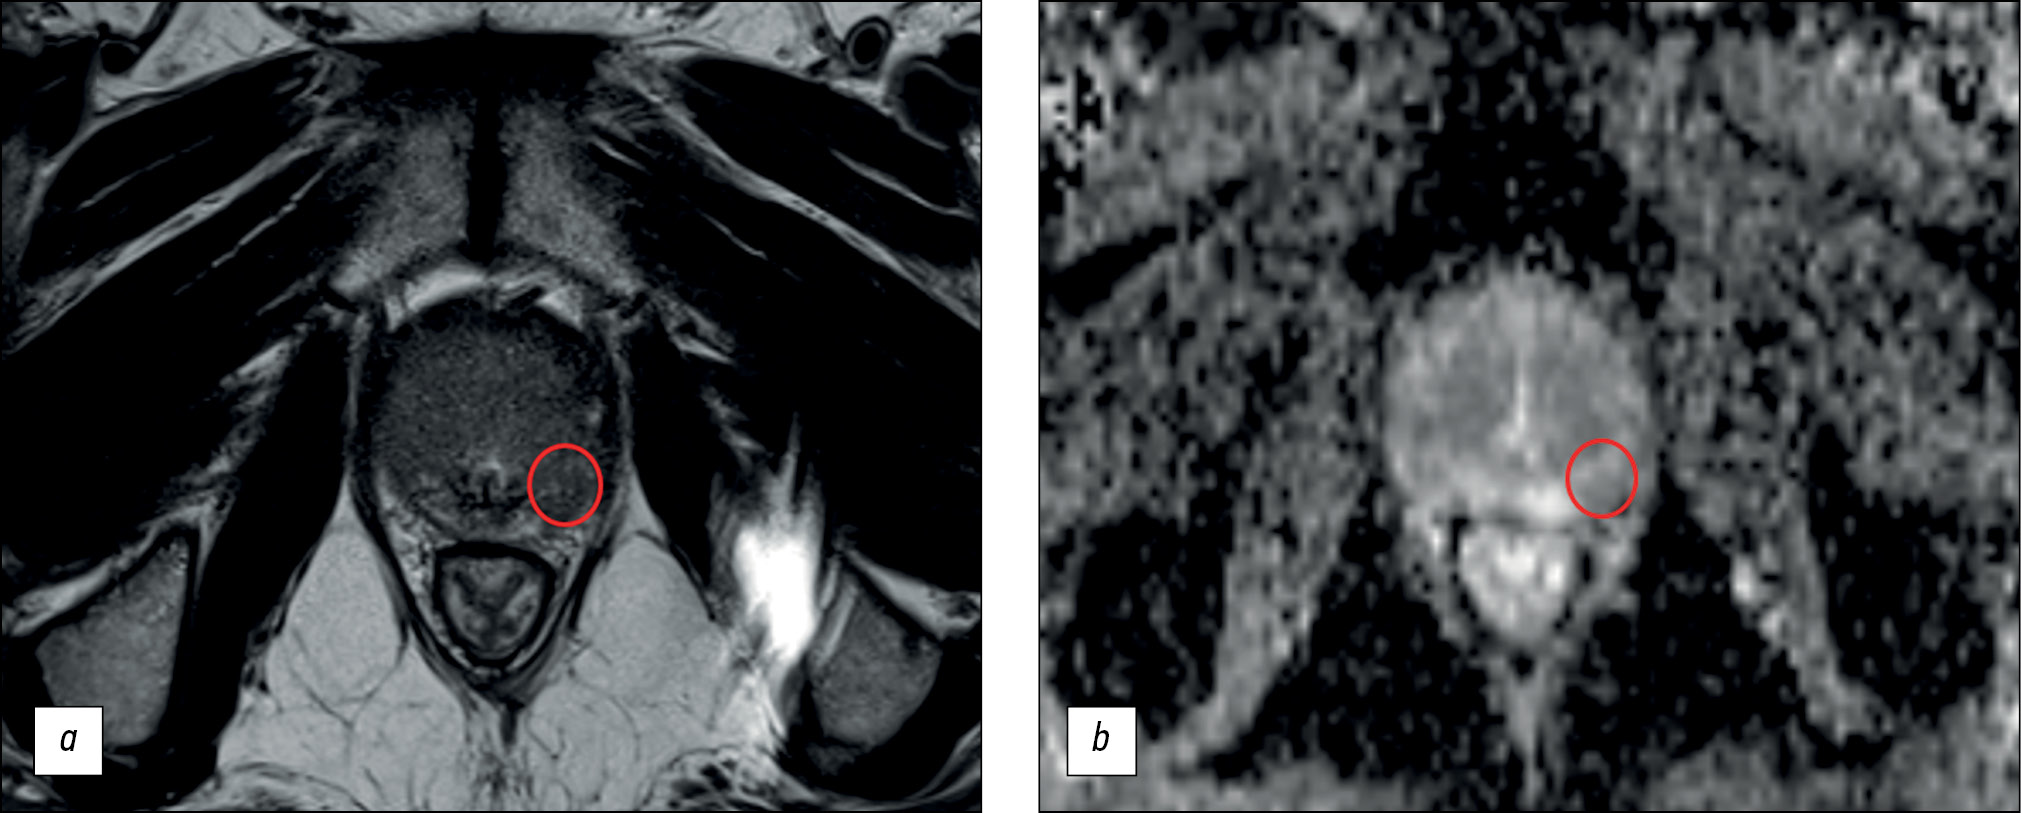

Сравнение мультипараметрического и бипараметрического протоколов магнитно-резонансной томографии для выявления рака предстательной железы рентгенологами с различным опытом

Обоснование. Проведение магнитно-резонансной томографии позволяет выявить клинически значимый рак предстательной железы, диагностировать экстракапсулярную экстензию, стадировать онкологический процесс. Протокол сканирования, включающий только Т2-взвешенные и диффузионно-взвешенные изображения, представляет собой жизнеспособную альтернативу мультипараметрической магнитно-резонансной томографии при условии сохранения высокой диагностической точности теста. В недавних исследованиях диагностическая точность бипараметрической и мультипараметрической магнитно-резонансной томографии в выявлении рака предстательной железы продемонстрировала незначительные различия.

Цель ― сравнение диагностической точности бипараметрической и мультипараметрической магнитно-резонансной томографии для выявления клинически значимого рака предстательной железы по системе PI-RADS v2.1 с использованием мультифокальной биопсии под контролем магнитно-резонансной томографии в качестве золотого стандарта.

Материалы и методы. Данное исследование является ретроспективным. Мы изначально обработали записи историй болезни 126 пациентов. Критериями включения в исследование были наличие мультипараметрической магнитно-резонансной томографии по стандарту PI-RADS 2.1, клинической информации об уровнях свободного и связанного простатспецифического антигена крови, мультифокальной биопсии предстательной железы при соблюдении временного интервала между магнитно-резонансной томографией и биопсией не более 14 дней. Три исследователя (врачи-рентгенологи с опытом работы менее 2 лет, от 2 до 5 лет, более 5 лет соответственно) независимо друг от друга оценивали бипараметрическую магнитно-резонансную томографию предстательной железы на предмет наличия патологических очагов. Спустя 2 недели исследователи оценивали датасет мультипараметрической магнитно-резонансной томографии предстательной железы. Каждый выявленный очаг, начиная с категории PI-RADS 3, сопоставлялся с результатом мультифокальной фьюжн-биопсии. Результат биопсии представлялся в виде суммы значений по шкале Gleason, при этом к клинически значимым данным биопсии относилась сумма Gleason 7 и выше. Опухолевыми очагами по данным магнитно-резонансной томографии считались находки, соответствующие критериям PI-RADS 4 и 5.

Результаты. Наилучшие показатели чувствительности и специфичности выявления очагов на магнитно-резонансной томографии предстательной железы ― 62,5 и 74,6% соответственно. Наивысшая достигнутая диагностическая точность составила 70,1%. Мультипараметрическая магнитно-резонансная томография обладает более высокими показателями специфичности выявления очагов предстательной железы при интерпретации рентгенологами с опытом работы менее 2 лет и более 5 лет.

Заключение. Как бипараметрическая, так и мультипараметрическая магнитно-резонансная томография предстательной железы продемонстрировала неоптимальные показатели диагностической точности. Имеется тенденция к улучшению чувствительности и специфичности метода с увеличением опыта работы рентгенолога. Бипараметрические протоколы сканирования предстательной железы имеют безусловное экономическое преимущество перед мультипараметрическими за счёт отсутствия расходов на контрастное вещество и расходные материалы и значительного снижения времени загрузки МР-сканера, однако их использование может привести к снижению диагностической точности метода.